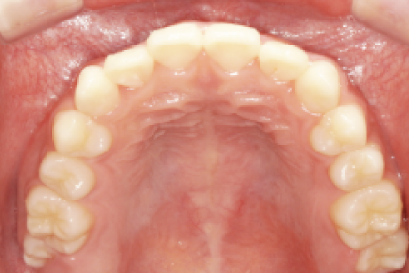

術後

年代、性別

10代、女性

職業

学生

主訴

歯並び相談

部位

インビザラインによる全顎矯正

治療期間

6ヶ月

矯正費用

95万円

施術説明

インビザラインによる全顎矯正。成人式まで期間がない中、綺麗な写真で成人式を祝いたいという事でお母様と来院されました。見た目への支障で悩んでいましたが、検査の結果アライナー矯正が可能と判断し半年で矯正を完了できました。成人式の記念撮影にも間に合い、非常に喜んで頂けました。

副作用・リスク

なし